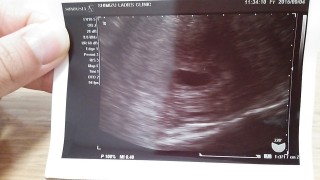

不正出血があって急遽病院行きました(^◇^;) 子宮外妊娠とかではなく正常妊娠ですよ~って言われて、 少しホッとした;^_^A これから無事に育って欲しいな(^_^*)